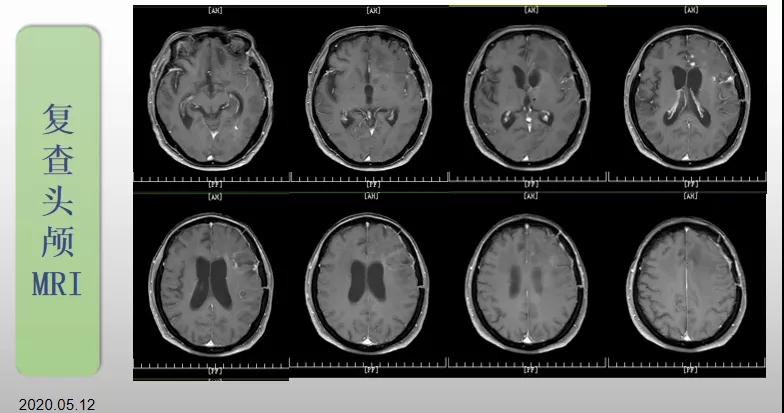

70歲的郝女士去年曾在外院查出“左額島葉”膠質(zhì)母細胞瘤(WHO Ⅳ級),并做了左側(cè)額島葉占位性病變切除術(shù)。術(shù)后進行了同步放化療。由于治療條件有限,郝女士慕名來到我院就診。賀世明主任率領(lǐng)醫(yī)護團隊立即為郝女士進行了全面的檢查,決定為其進行綜合治療 電場治療。經(jīng)過三個多月的綜合治療,患者復(fù)查頭顱MRI病變較前明顯縮小。出院時,郝女士神志清醒,睡眠飲食正常,說話很流利?!拔沂翘芍M來的,現(xiàn)在不用人攙扶,自己就可以走出病房了?!焙屡坷t(yī)護人員的手說。